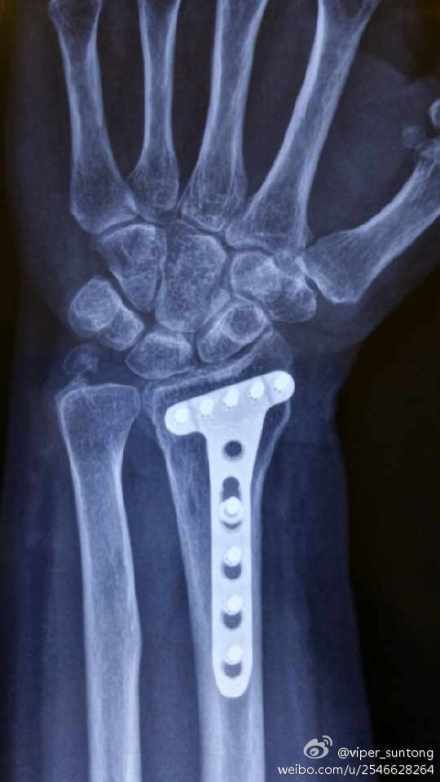

“孙大夫,我又来复查来了!”老太太见到我,兴冲冲地跑了过来,如家人般的亲切。我也赶紧迎上前,招呼她进屋坐下。这是我半年前手术的一个病人,桡骨远端粉碎性骨折。当时的她对手术充满了疑虑与焦虑!患者对手术的恐惧心理与不确定心理,作为一名临床大夫,我是很能体会的。在与她进行了一次长谈之后,她最终还是选择了手术治疗她的骨折。这次来复查,我给她拍了手术部位的X线。术后半年了,桡骨骨折愈合良好,内固定钢板位置也很理想。检查她腕关节的功能,真的很满意(如图)。当我告诉她,她术后的恢复很不错的时候,老太太开心地笑了,向我竖起了大拇指!